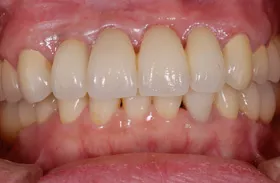

■治療前:上下顎 義歯での食事に満足されていない

■治療後:上下顎 複数本のインプラントを使い固定式で治療

| 主訴 | 現在義歯を使用しているが、しっかりと咬んでなんでもおいしく食事したい |

| 治療方法 | 上下顎 複数本のインプラントを使用しての治療 |

| 治療期間 | 約1年 |

| 通院回数等 | 約20回 |

| 費用 | 約600万円(税込) |

| リスク・副作用 | 術後の腫れ・痛み |